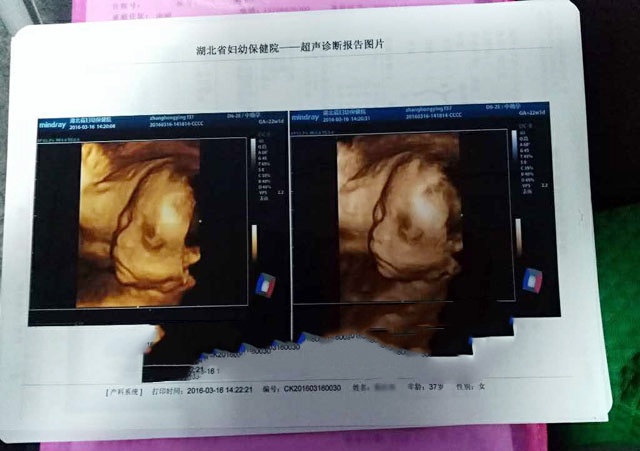

2015年8月2日,Z女士获卵12枚,取卵第三天胚胎10个,取卵第6天囊胚4枚。

历经一个月的等待,9月12日,Z女士4枚囊胚中,3个男孩,1个女孩。其中一个男孩存在染色体异常,不符合移植标准,还有两个健康男孩囊胚,可以移植。

2015年11月1日,移植两个XY男孩胚胎。